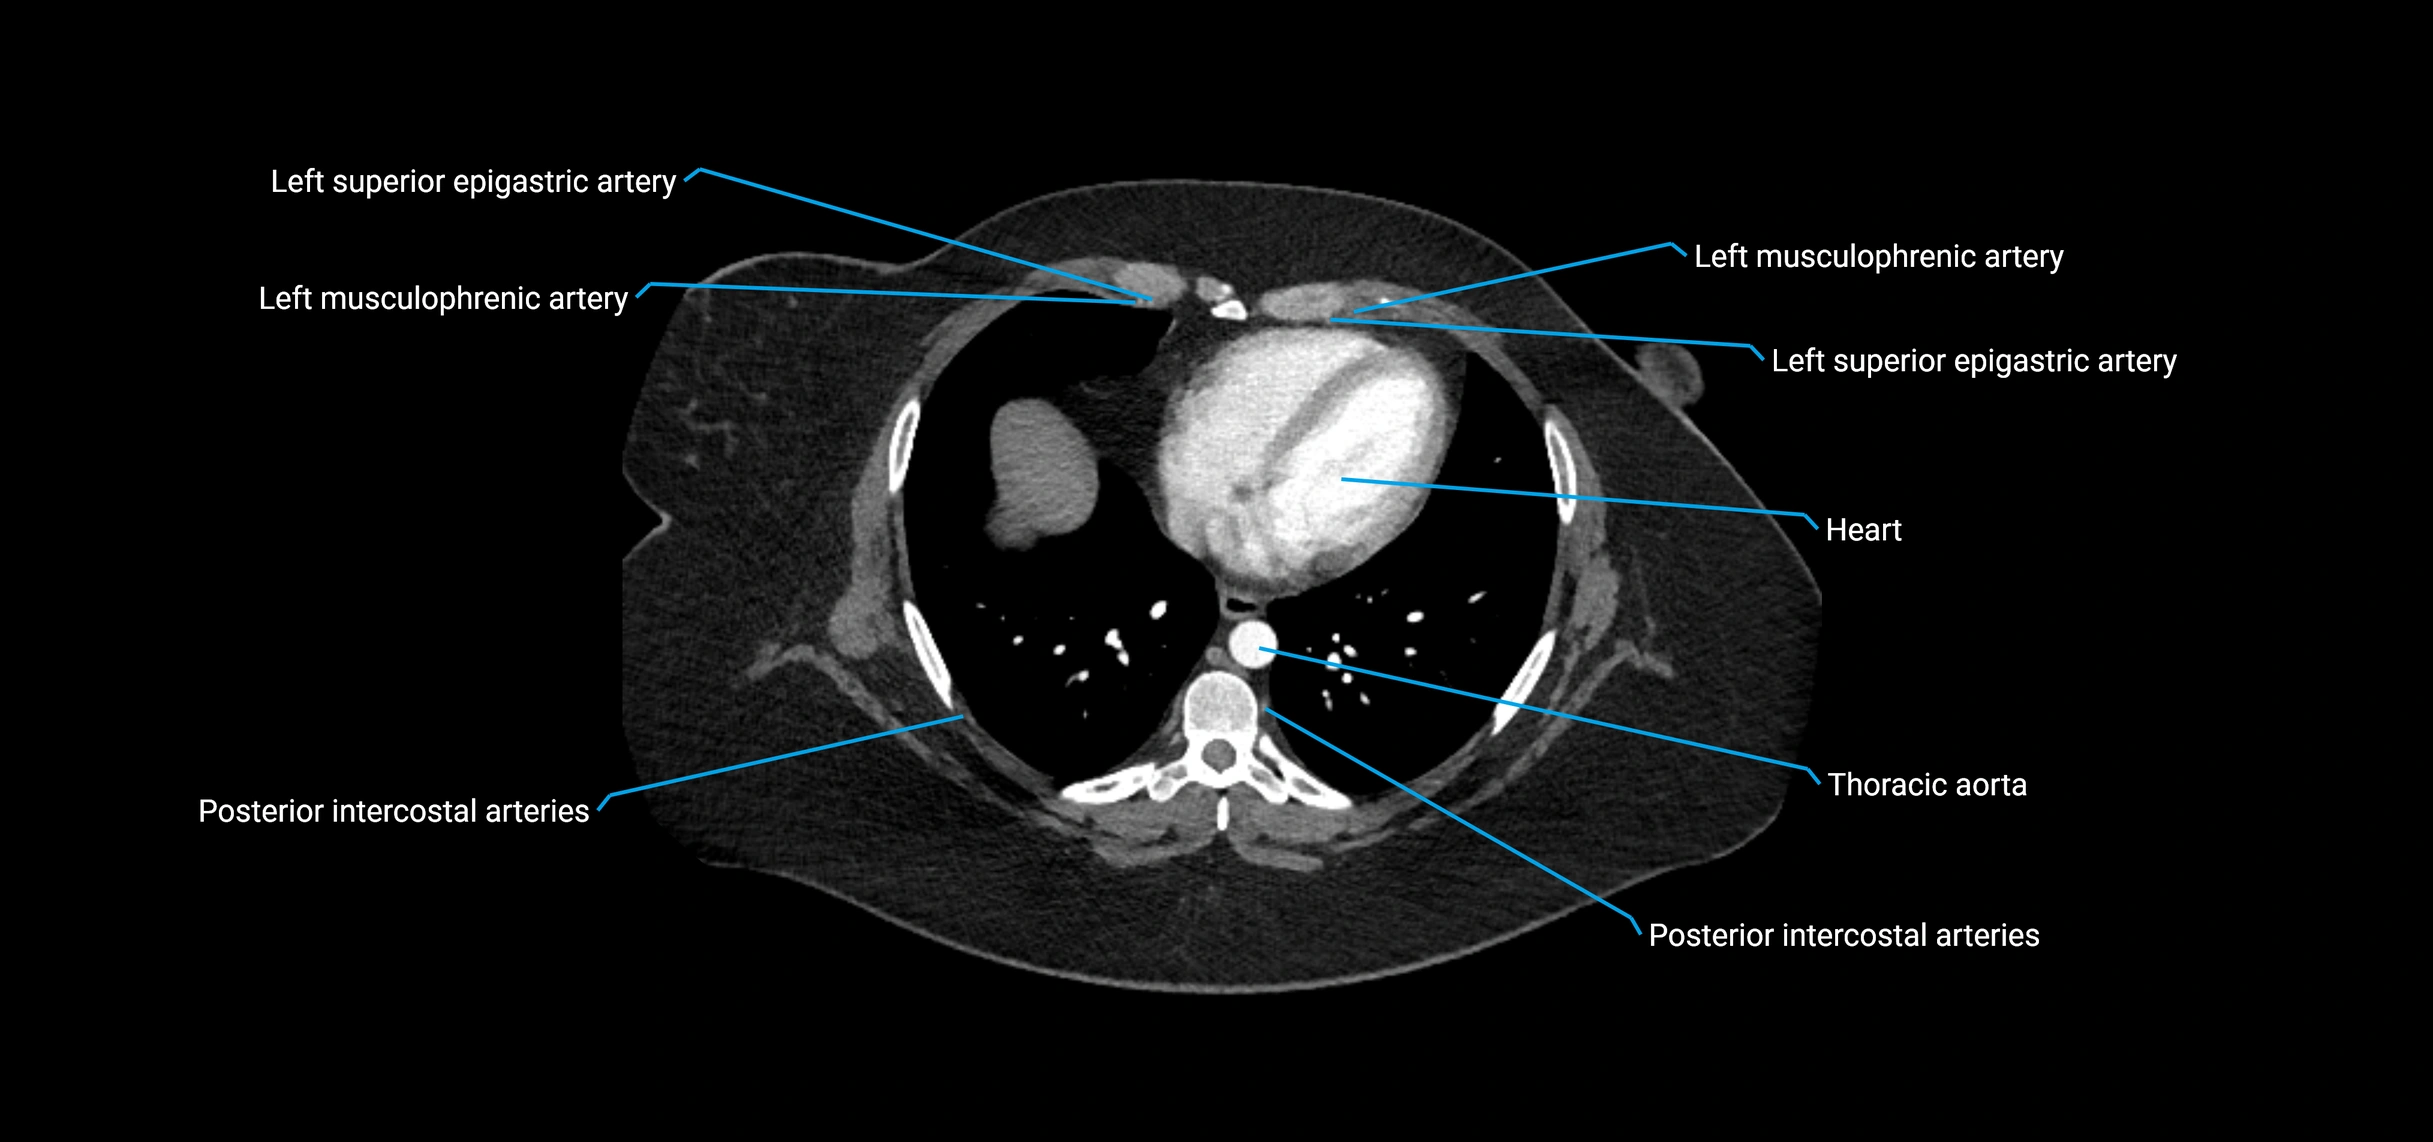

CT images

image

CT Appearance

Non-contrast CT:

• Appears as a tubular soft tissue structure anterior to vertebral bodies

• Calcified atherosclerotic plaques appear as hyperdense foci along the wall

• Useful for screening abdominal aortic aneurysm (AAA) size and mural calcification

Contrast-enhanced CT (CTA):

• Gold standard for abdominal aortic imaging

• Provides excellent detail of lumen, wall, aneurysm, thrombus, and branch vessels

• Multiplanar and 3D reconstructions help in aneurysm measurement, stent graft planning, and dissection evaluation

• Detects acute rupture, traumatic injury, or occlusion with high sensitivity